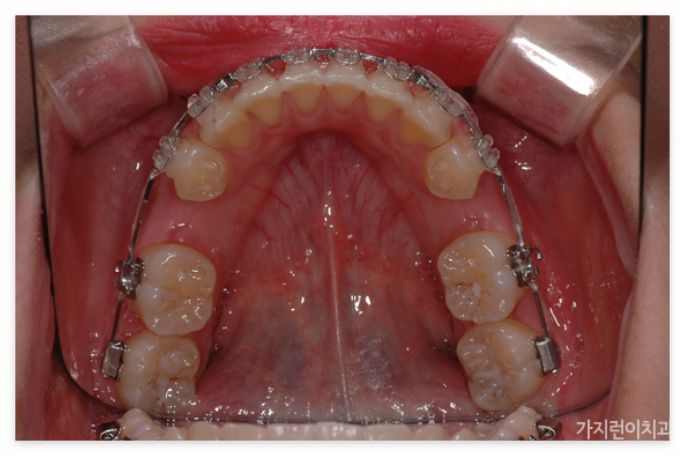

앞으로 돌출된 치아를 집어넣으려면

앞으로 돌출된 치아를 구조적으로 안쪽으로 집어넣기 위해서는 공간의 확보가 필요합니다. 그래서 많은 분들이 발치를 진행하는데요. 위와 같은 경우도 상하악 제1소구치를 발치한 후에 충분한 공간을 확보한 후에 진행을 하였습니다. 특히 발치가 무조건 안 좋고 비발치가 좋은 것이라고 오해하는 경우가 있는데 발치할 케이스임에도 비발치로 진행하게 되면 오히려 더 안 좋은 결과를 안아볼 수 있기 때문에 상악 전치의 후방이동을 위한 충분한 공간확보를 위한 과정이라고 이해하면 되겠습니다. 본원에서는 서울 거미스마일 교정을 위해 미니스크류를 식립해 상악 전치를 위로 올리는 힘을 추가 했습니다. 미니스크류를 이용하면 개선할 충분한 힘이 가해지기 때문에 상하악 전치가 동시에 이동할 수 있습니다.